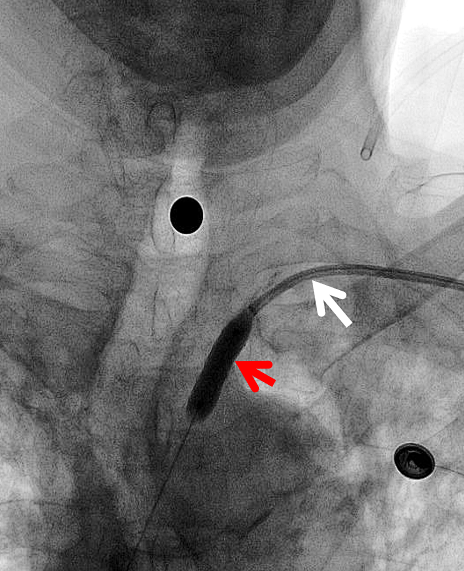

6F NeuronMax 建立良好的支撑【白箭头】,支架顺利对位

NeuronMax头端顺应性良好【白箭头】,球囊扩张支架充分